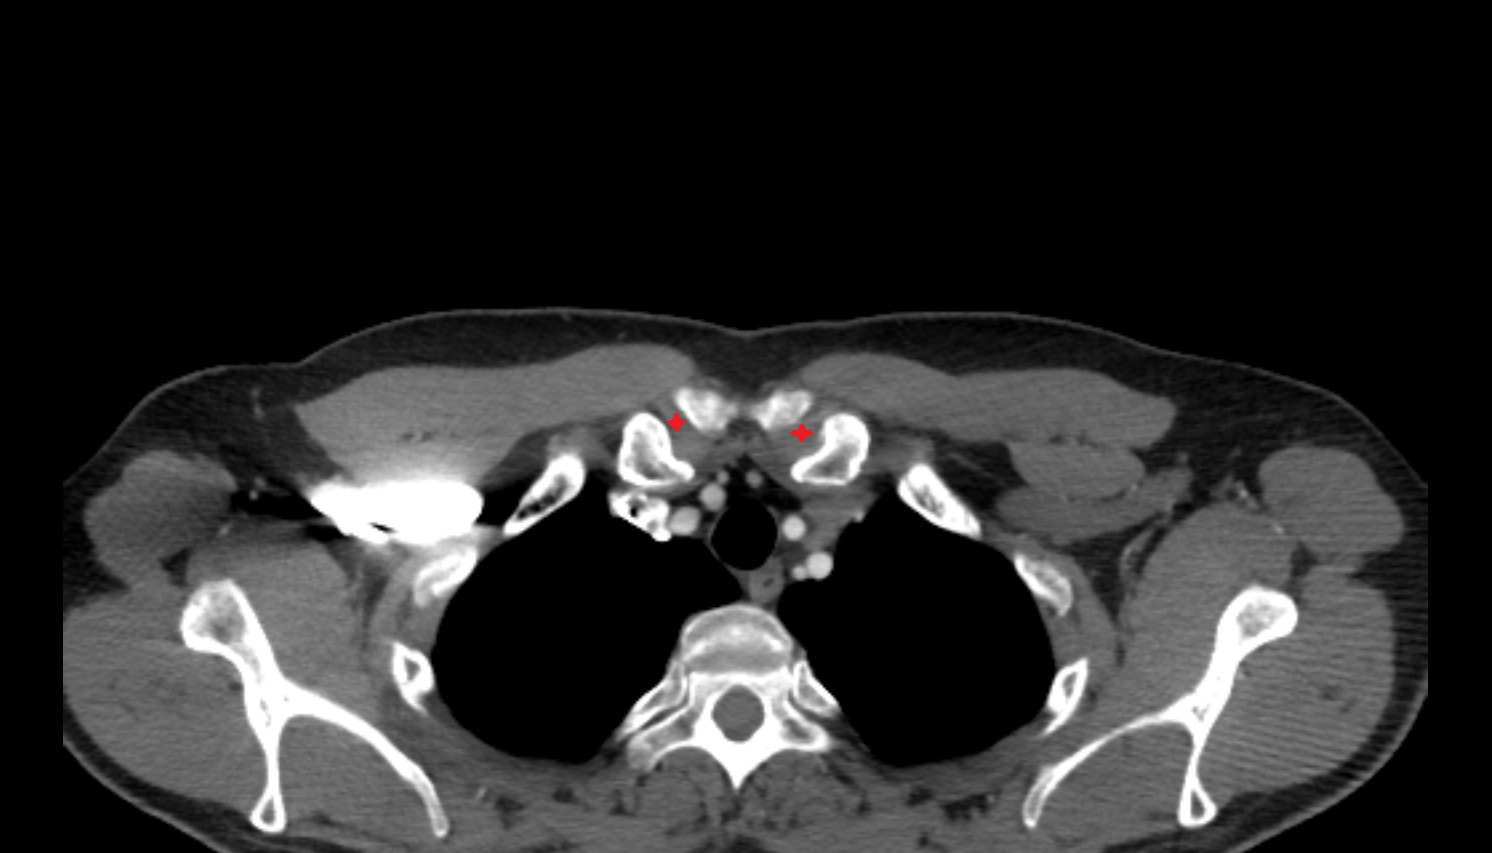

- Carotid bifurcation

- Common carotid artery

- External carotid artery

- Internal carotid artery (cervical part)